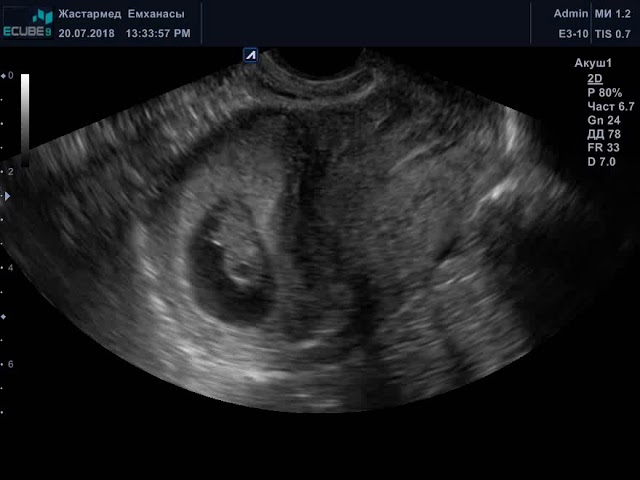

Плодное яйцо – признак беременности. Это округлое или яйцеобразное образование, расположенное вокруг эмбриона, анэхогенное (не отражает ультразвук из-за жидкости внутри), со средним внутренний диаметром (СВД в протоколе УЗИ) от 24 до 30 мм.

В 8 недель беременности эмбрион выглядит так:

- длина 2 см;

- личико приобретает человеческие черты;

- формируются пальчики на ручках и ножках;

- просматривается позвоночный столб;

- размер головы равен половине длины туловища – активно растет мозг;

- развиваются органы дыхания и печень, формируются желчные протоки;

- желудок и кишечник уже оформлены;

- сформировано и начинает работу сердце;

- почки готовятся приступить к фильтрационной функции;

- плод начинает совершать первые движения;

- образуется пуповина;

- уменьшается хвостик;

- вес крохи приближается к 1,5 г.

В 8 недель определяют КТР – копчико-теменной размер. В норме – 14-18 мм. Уменьшение говорит о возможной задержке развития, пороках или аномалиях строения. Небольшие отклонения на малом сроке не всегда указывают на проблему. С последующим ростом плод догоняет норму.

8 недель беременности – время, когда можно услышать стук сердца малыша. Частота сердечных сокращений подсчитывается с помощью УЗИ. За норму приняты показатели от 110 до 150 уд/мин. Оценивается не только частота ударов сердца, но и ритмичность.